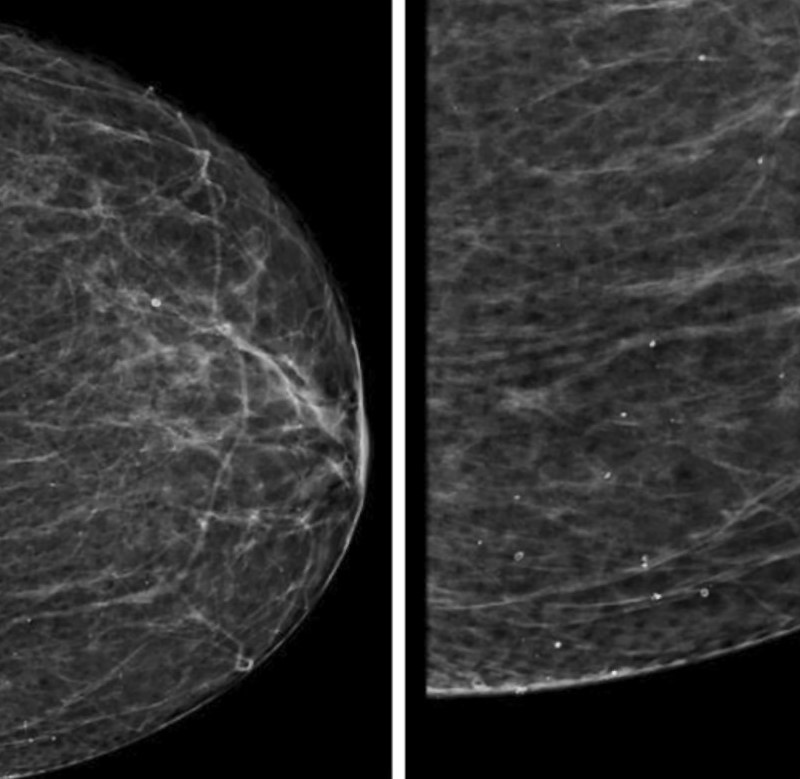

В данном проспективно-ретроспективном исследовании был проведен анализ результатов маммографического исследования 1030 пациенток, проходивших диспансеризацию в Университетской клинике МНОИ МГУ имени М.В.Ломоносова в период с 2019 по 2023 год. Для адекватной трактовки результатов инструментальной диагностики РМЖ была использована система BI-RADS (Breast Imaging Reporting and Data System). Оценка плотности молочных желез проводилась на основании шкалы, разработанной Американским колледжем радиологии (англ. – ACR - American College of Radiology) [9]. Согласно этой шкале, выделяют 4 типа молочных желез (Рис.1):

А – МЖ практически полностью жировой плотности (термин "плотность" здесь и далее в данном контексте характеризует степень ослабления рентгеновского излучения при прохождении через ткань молочной железы). Маммография обладает высокой чувствительностью.

В - Отдельные участки фибро-гландулярной (фиброзно-железистой) низкой рентгенологической плотности.

С - МЖ неоднородной (гетерогенной) высокой плотности, либо отдельные участки молочных желез достаточно плотные и могут скрывать небольшие образования.

D - Очень плотные МЖ. Маммография обладает низкой чувствительностью.